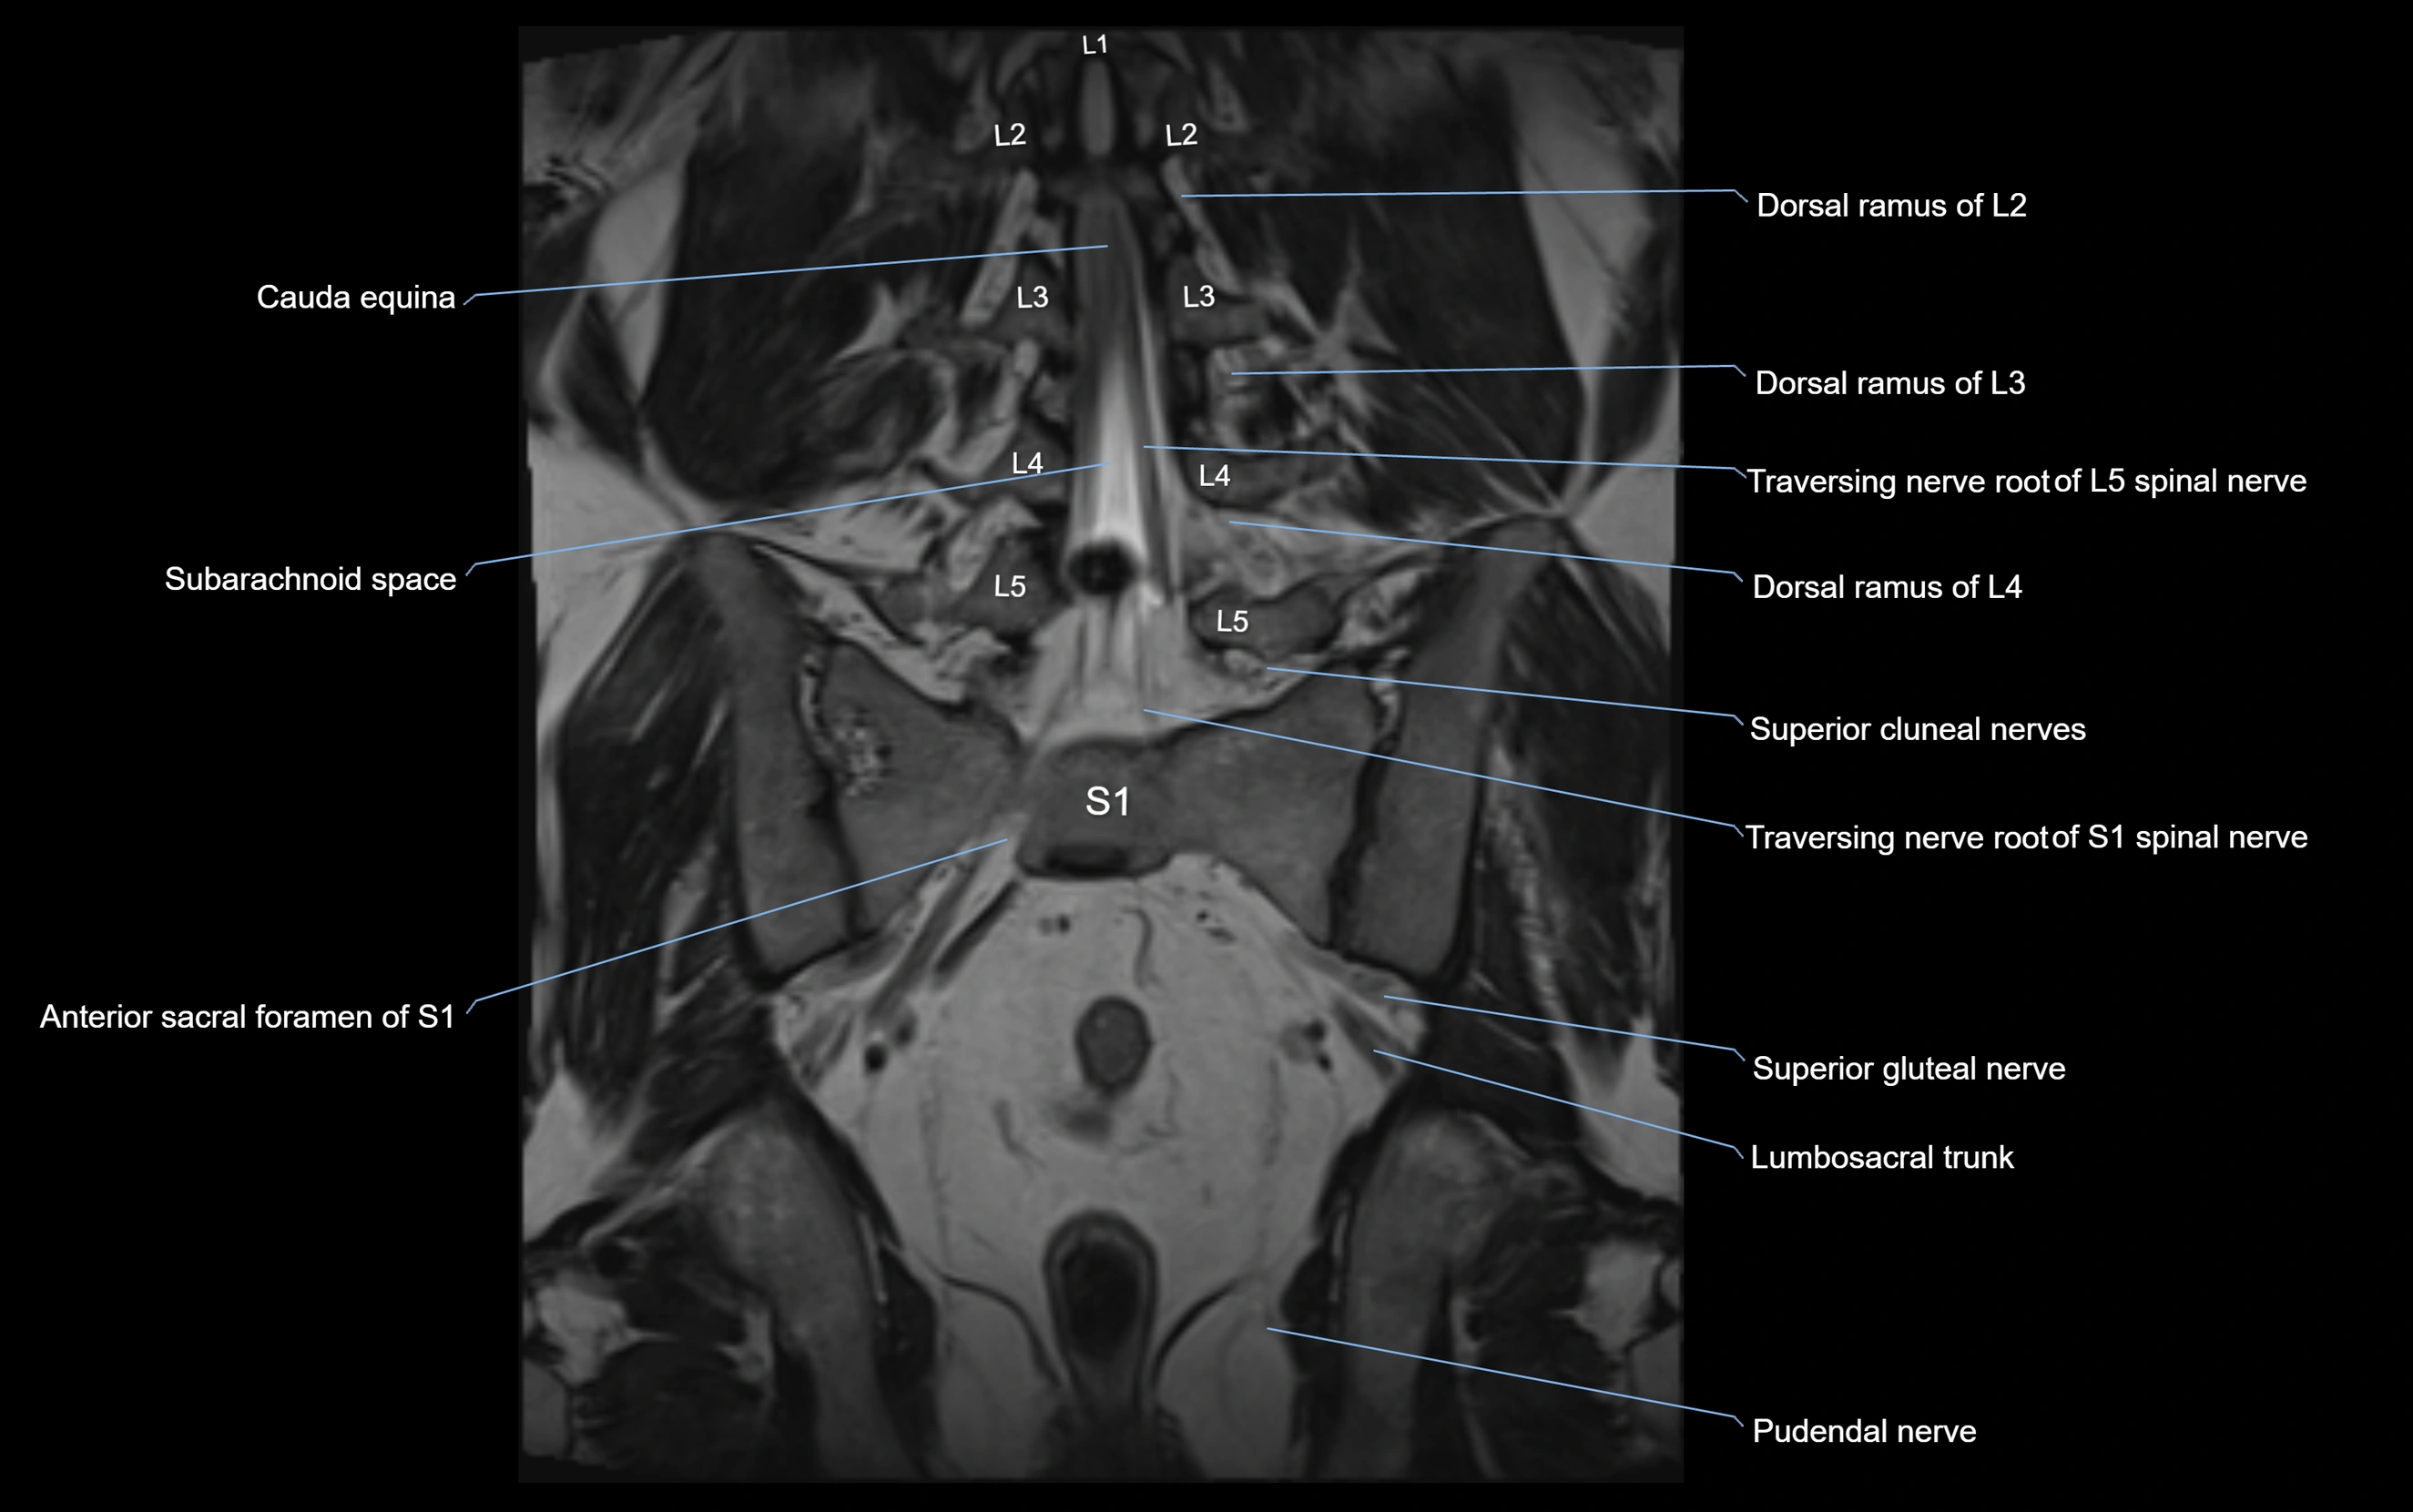

MRI image

image